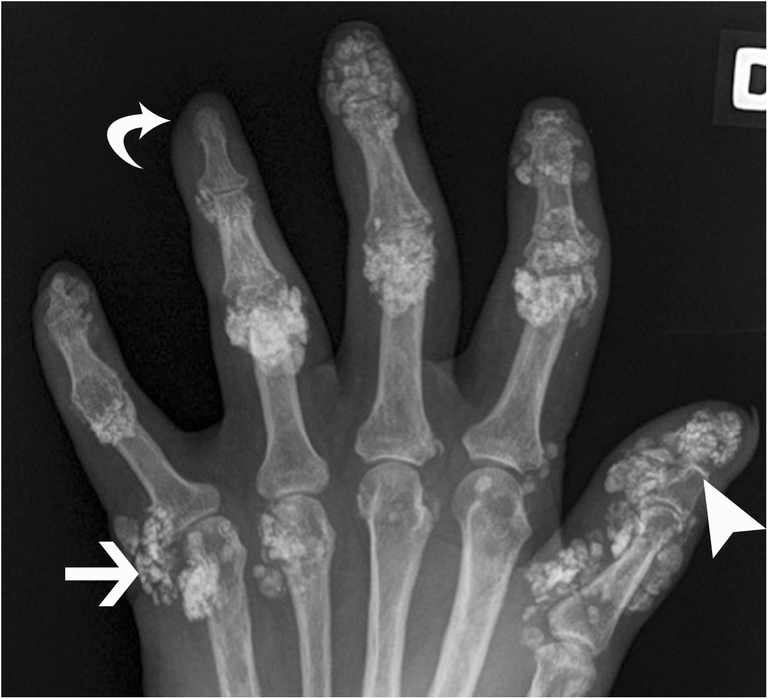

Widespread soft tissue calcification in systemic sclerosis Hand Soft Tissue Calcification Radiology These are listed below in order of prevalence. Posteroanterior radiograph of the hand shows tumoural calcinosis in the soft tissue (arrow). Soft tissue calcifications are usually caused by one of the following six entities. Common causes of periarticular soft tissue calcification include: There is a wide range of. Soft tissue calcification is commonly seen and caused by a wide range. Hand Soft Tissue Calcification Radiology.